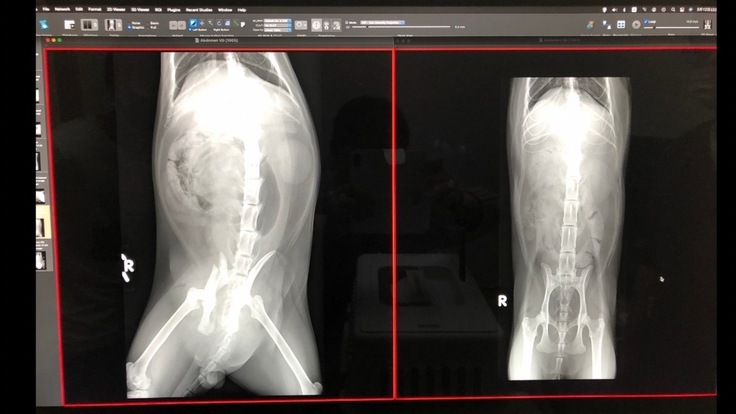

病院に運ばれた日向は、呼吸促拍、抑うつ状態、腰部の疼痛、左後肢の麻痺、骨盤骨折と診断され、かなり衰弱していました。3月19日まで入院治療をした結果、自力で排尿もできるようになり、食欲も戻ってきました。ただ、骨盤を骨折しているため、整復手術が必要で、手術後も麻痺などの後遺症が残る可能性があるとのことでした。

手術前のレントゲン

手術内容 ⑴骨盤骨折:右腸骨体骨折はプレート固定、左仙腸関節脱臼は元の場所に戻してスクリューで固定してもらいました。 ⑵右大腿骨頸部骨折:事故から2週間以上経っていて治ってきているのでこのまま自然治癒という形をとります。将来関節炎になる可能性があるとのこと。大変な手術でしたが、日向は頑張りました。病院でも看護師さんになつき、順調な回復を見せました。